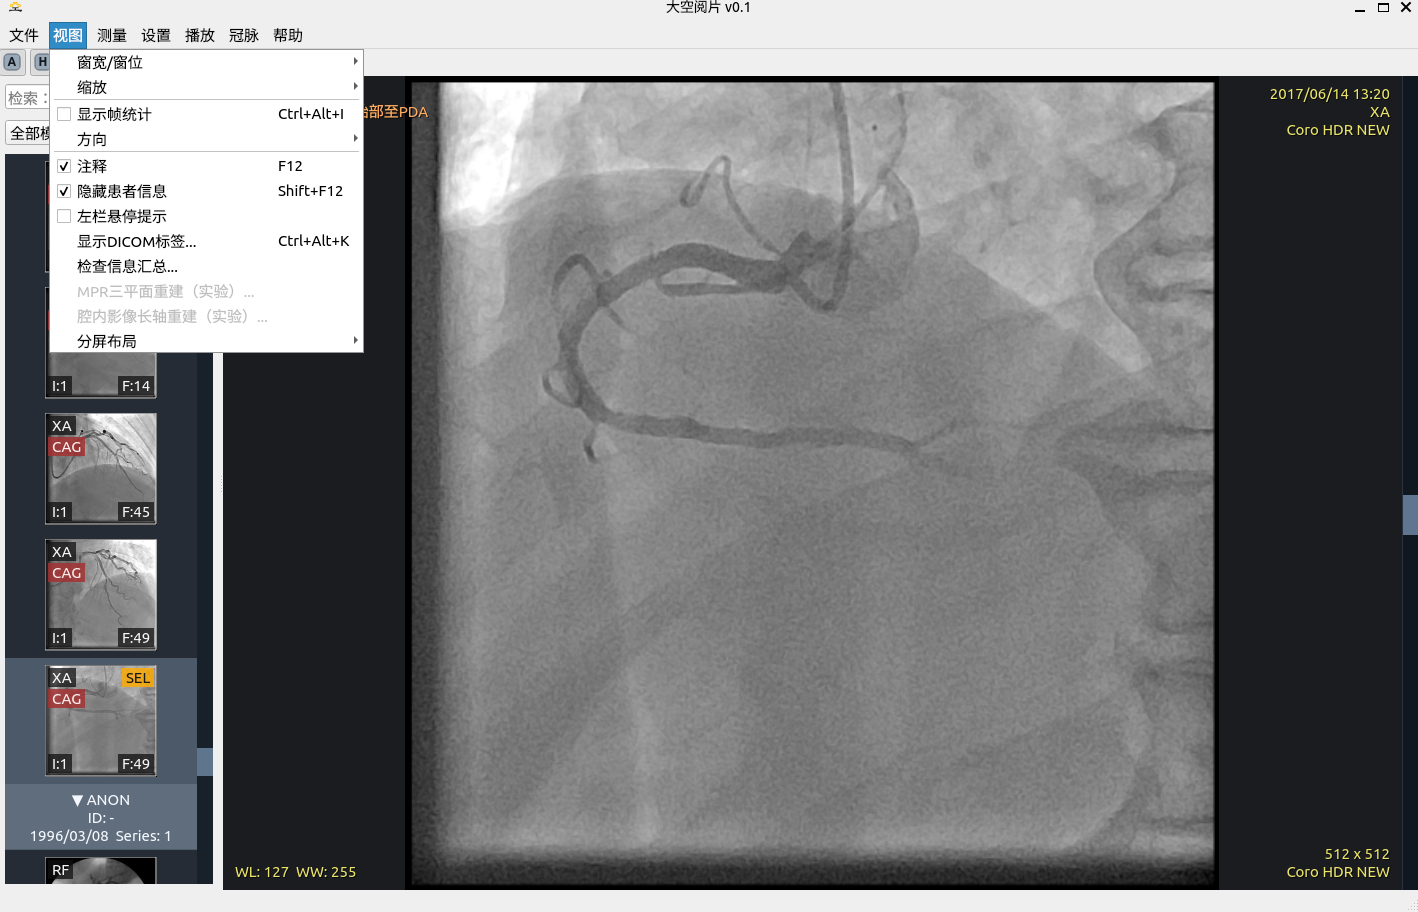

10. 隐藏患者信息

为教学演示、会诊共享与院内讨论提供隐私保护支持。

• 可切换患者信息隐藏显示,降低外泄风险。

• 与常规阅片流程兼容,不影响核心交互。

• 支持在演示与导出场景保持一致隐私口径。

隐藏患者信息

患者信息隐藏示例